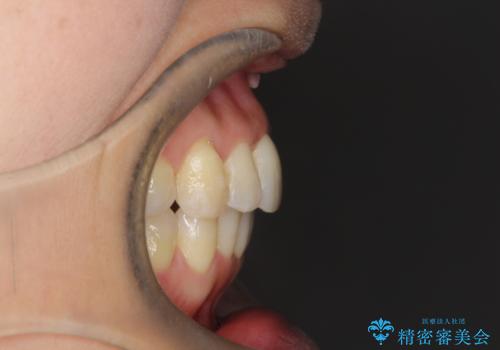

重度のガタガタのインビザラインによる非抜歯矯正

- 上下の歯のガタガタを主訴に来院されました。

インビザラインで奥歯を後方に移動させるのと、歯と歯の間をわずかに削ることでスペースを作り、歯を並べる計画としました。